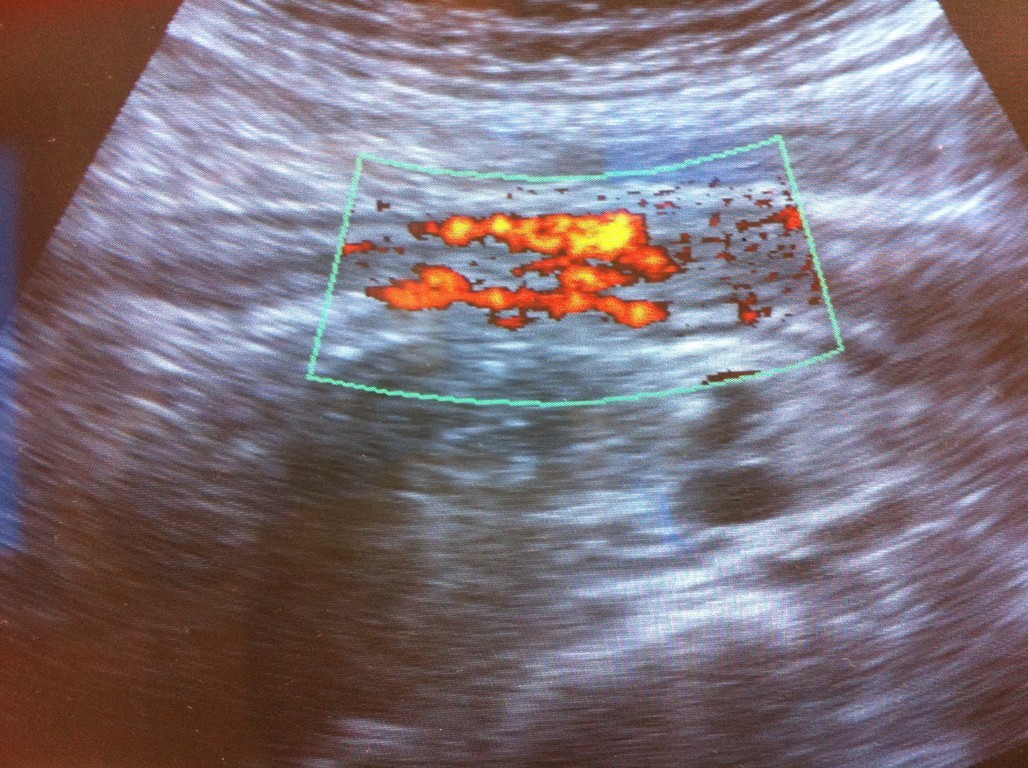

Oltre all'ecografia gastrointestinale, l'ecografia tiroidea rappresenta un altro campo specialistico di vasta esperienza con esecuzione della diagnostica base, il colordoppler e doppler tiroide e lo studio elastografico delle lesioni nodulari tiroidee altrimenti detta elastografia. Questa metodica permtte lo studio della elasticità dei tessuti e considerando che i tessuti neoplastici tendono ad essera di consistenza aumantata, l'elastografica ci aiuta a selezionare i noduli da sottoporre ad campionamento citologico con FNAB.